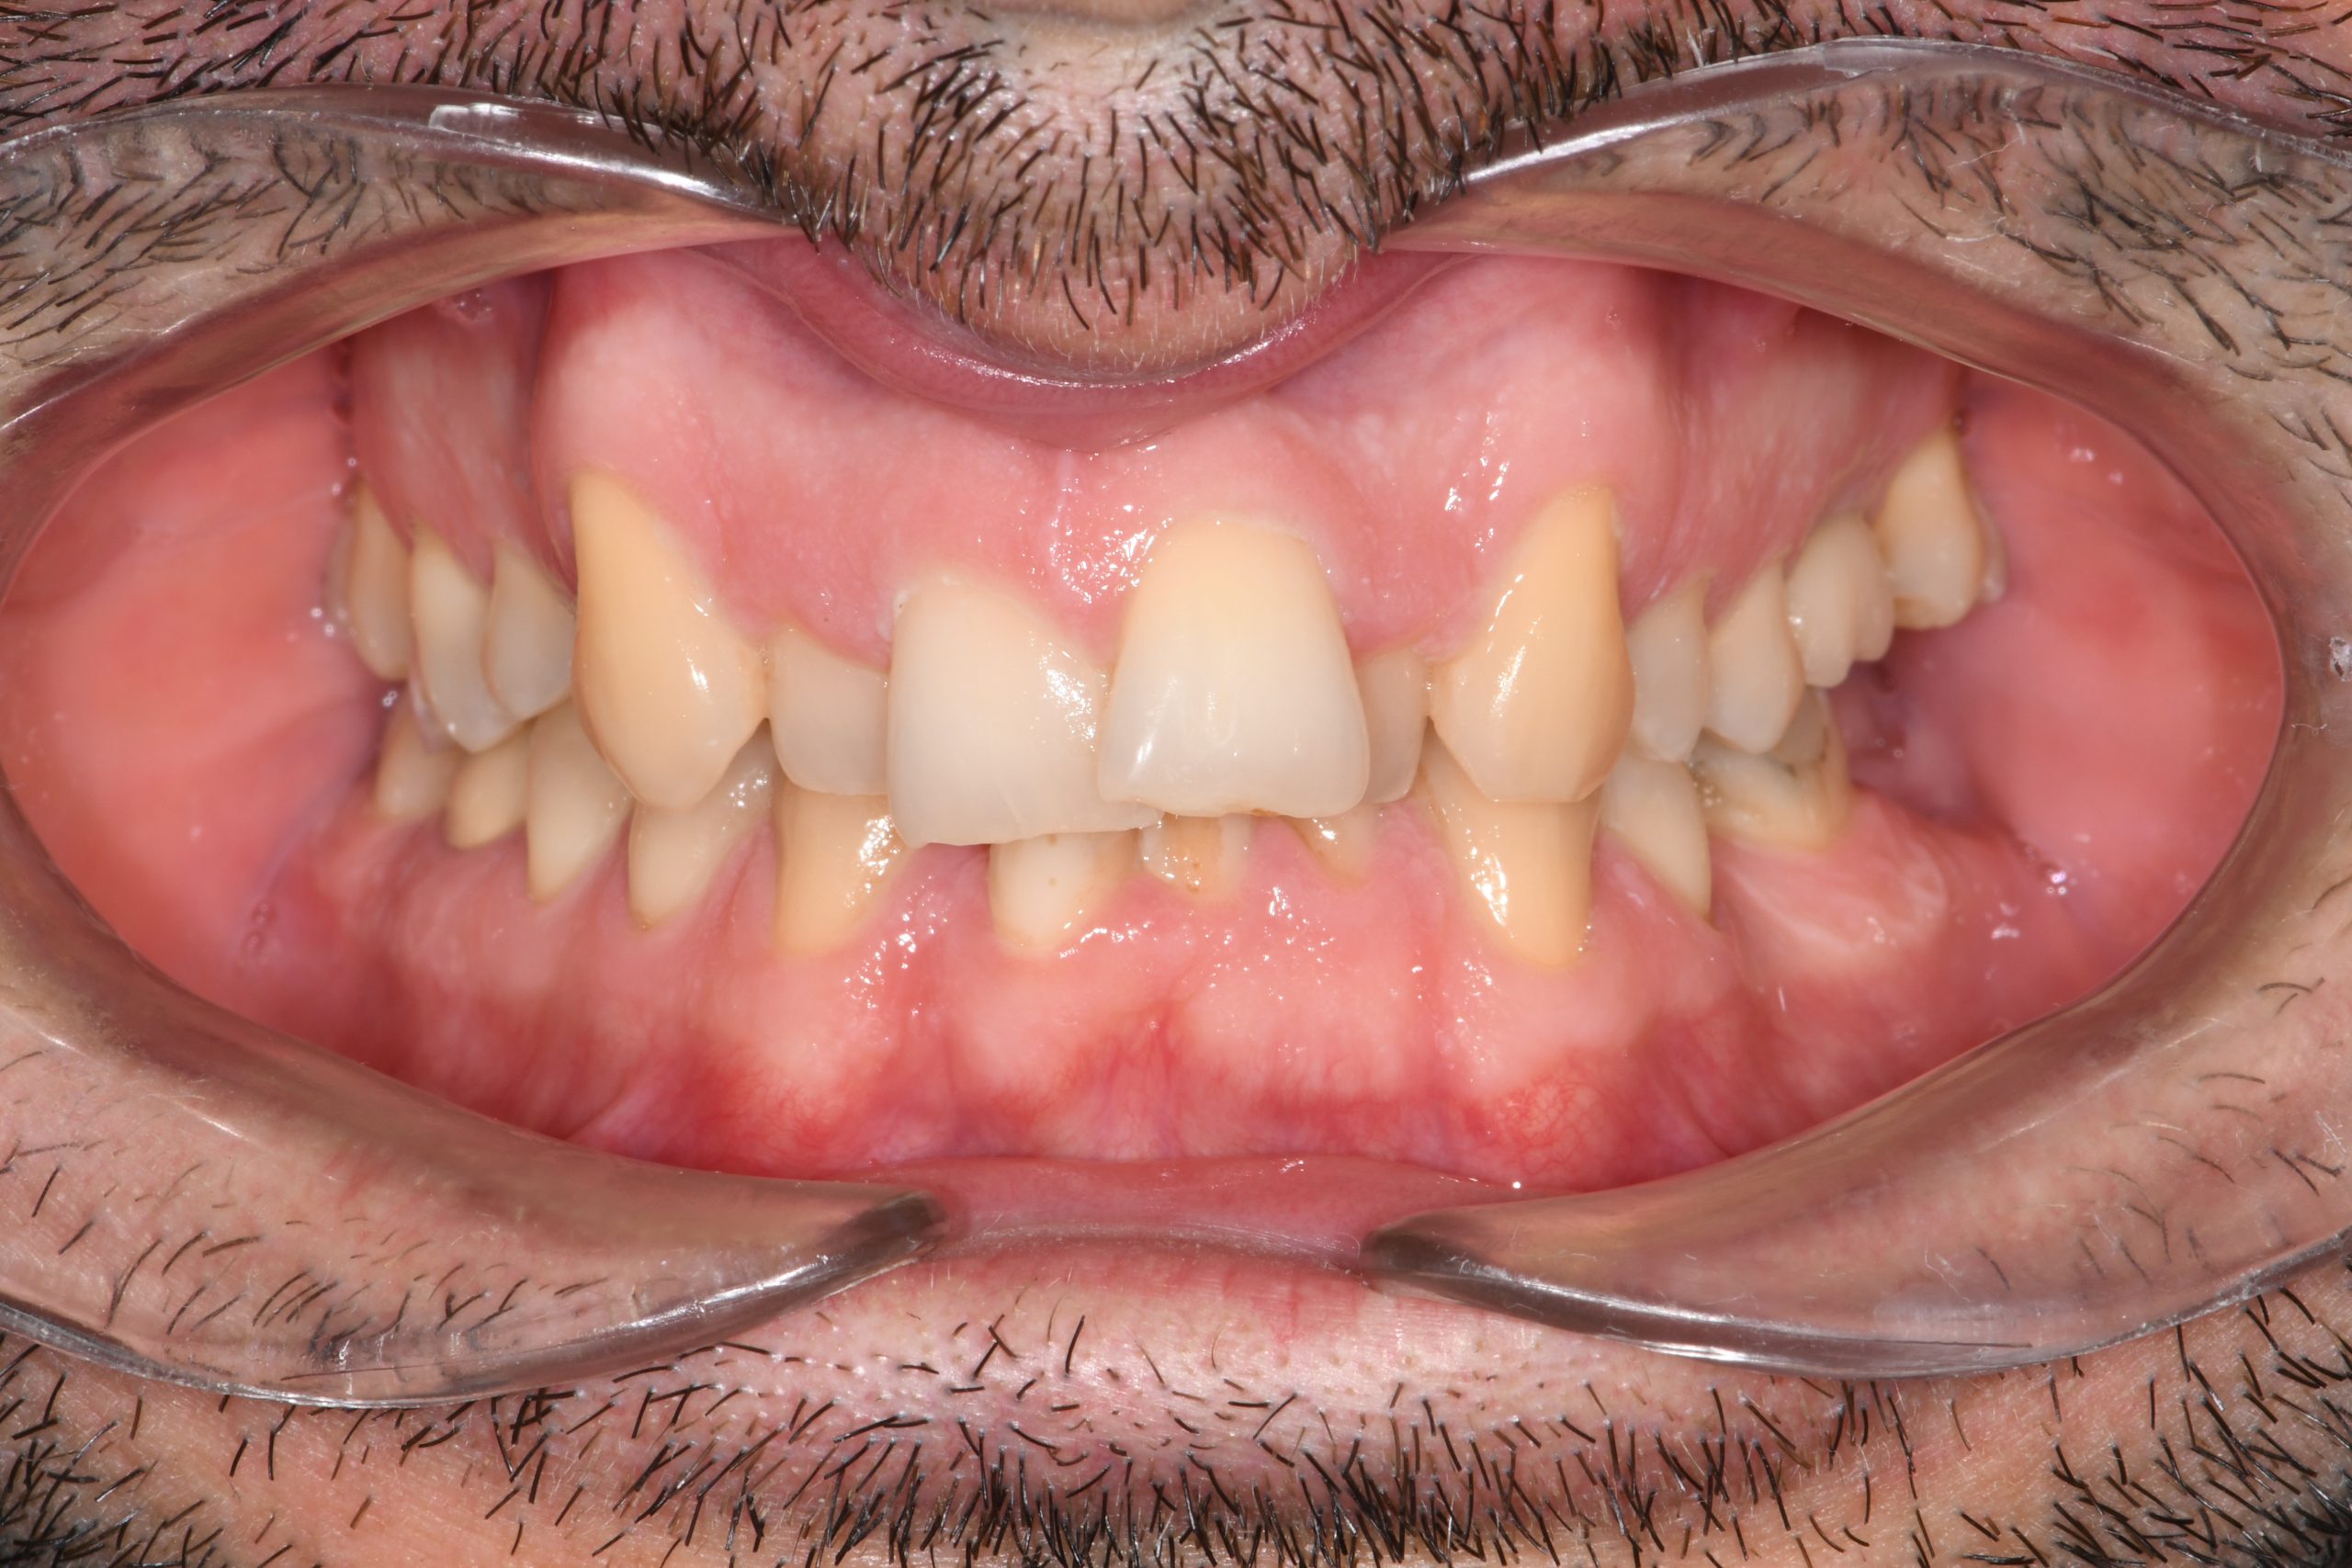

Az elmúlt évekből rengeteg szakmai referenciát tudnánk bemutatni, amelyek különböző fogszabályozási problémákat oldottak meg. Válogatva a több száz esetből, ezen az oldalon olyan képeket, információkat igyekeztünk bemutatni, amelyeknek a segítségével a jövőbeni pácienseinknek azt tudjuk üzenni: A Te fogsorod is lehet gyönyörű!

(Képeket a Pácienseink külön írásos beleegyezésével mutatjuk be!)